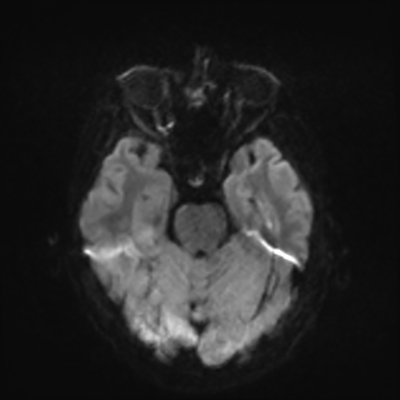

MRI brain (DWI)

You can clearly see diffuse cortical and basal ganglia diffusion restriction, and that of his deep cerebellar nuclei as well. The right occipital lobe abnormalities are a little more prominent, but then you remember that he is known to have had a right occipital stroke weeks ago.

In reviewing his data, you know that he doesn't have any of the strong predictors of a poor neurologic prognosis. However, based on these findings on MRI, along with the absent reactivity on cEEG, you are able to tell the primary team and the patient's family that he is likely to have a poor prognosis, based on these multiple moderate predictors. Recovery is not completely impossible-- there is more uncertainty with this prognostication than if we were able to get SSEPs-- but you're very worried about his outlook and that any potential recovery would require a very protracted rehabilitation period. Given his high cervical cord injury level, tracheostomy would be required anyway. So, it comes down to whether his family thinks he'd want to pursue these aggressive measures.